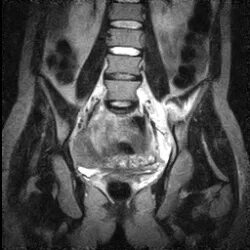

Сакроилеит на кт